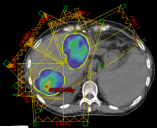

(1)、病例展示一:巨块型肝细胞肝癌合并门静脉癌栓

确诊肝癌并治疗后4月余复诊,伴有高热。腹部核磁:肝右叶异常强化灶,考虑肿瘤性病变;门静脉右支及门静脉主干管腔内见低密度影填充,考虑栓子形成。

病理诊断:肝细胞肝癌。治疗方案:碳离子放疗,总剂量:PTV:70Gy(RBE)/10Fx。同步治疗:阿替利珠单抗注射液+甲磺酸仑伐替尼胶囊。

影像学对比